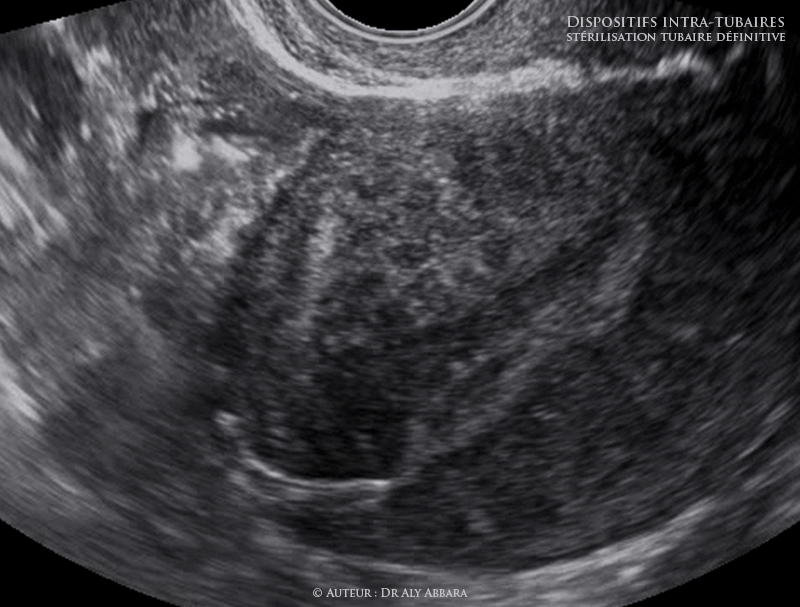

Utérus - Dispositif contraceptif définitif intra-tubaire - Aspects échographiques

Images échographiques animées montrant les différents aspects échographiques du dispositif contraceptif définitif intra-tubaire (DIT) correctement posé.

Cette méthode de stérilisation tubaire définitive qui fut commercialisée à partir de 2002, elle n’est plus commercialisée en France depuis le 18 septembre 2017.